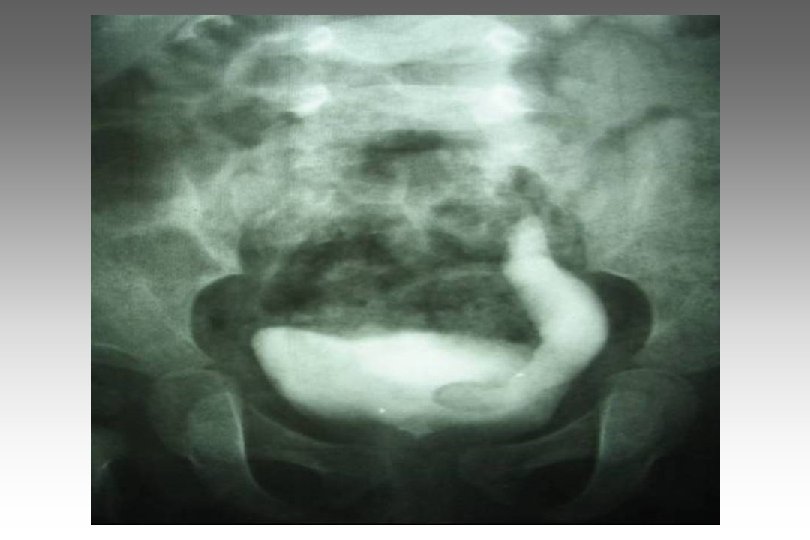

SECUENCIA DE IMAGEN o ECOGRAFIA. o CISTOURETROGRAFIA RETROGADA POST MICCIONAL. o PIELOGRAFIA ENDOVENOSA o GAMMAGRAFIA RENAL CON DMSA-TC 99. o RADIORENOGRAMA o UROGRAFIA POR RMN o TAC HELICOIDAL o ENDOSCOPIA VIRTUAL